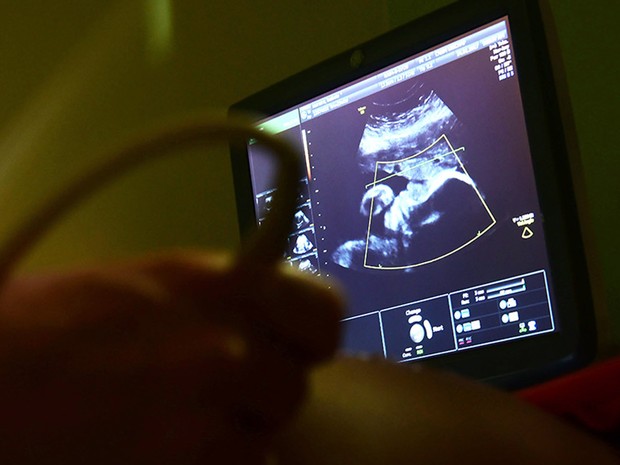

Para corrigir possíveis distorções em diagnósticos de crescimento fetal, a Organização Mundial de Saúde (OMS) recomenda o uso de uma nova referência, um padrão internacional de crescimento fetal que foi elaborado com ajuda da Universidade Estadual de Campinas (Unicamp) e que contou com a participação de 10 países.

O professor destaca que são vários as curvas de referência existentes para exames de ultrassonografia no mundo, mas que pela tradição de influência cultural e científica, é o padrão norte-americano o mais utilizado, o que pode causar distorções em algumas avaliações. “Esse é um padrão fundamentalmente baseado em mulheres de origem anglo-saxônica, brancas, onde o padrão de crescimento fetal é ligeiramente superior que esse padrão internacional.”

De acordo com Cecatti, no padrão internacional, todo o limite é “um pouco mais para baixo.” “Existe uma perspectiva, de quem trabalha com aparelho de ultrassom, principalmente em países de média renda, como é o caso do Brasil, de mudar esse padrão americano de referência que já vem embutido nos aparelhos, atualizando-o para a curva internacional da OMS”, aponta Cecatti.

As curvas de crescimento aferidas no estudo trazem informações sobre circunferência da cabeça e do abdome, do comprimento do úmero (o osso que vai do ombro ao cotovelo) e do fêmur, além de estimativas do peso do feto, feitas a partir dessas medições.